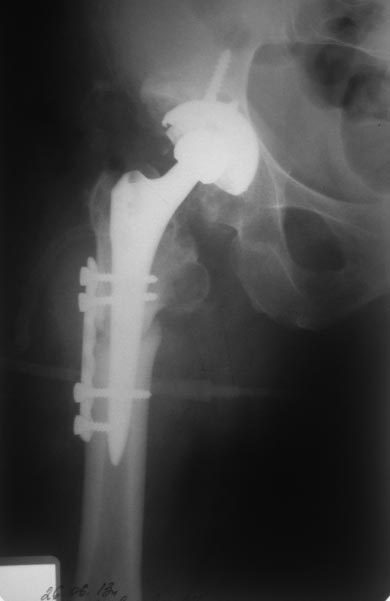

На днях прооперировали. Основная проблема была при обработке

проксимльного фрагмента поле остеотомии. Были сложности с адаптацией

фрагментов но контакт достаточный,  стабильность хорошая, надеюсь что

проблем со сращением не будет